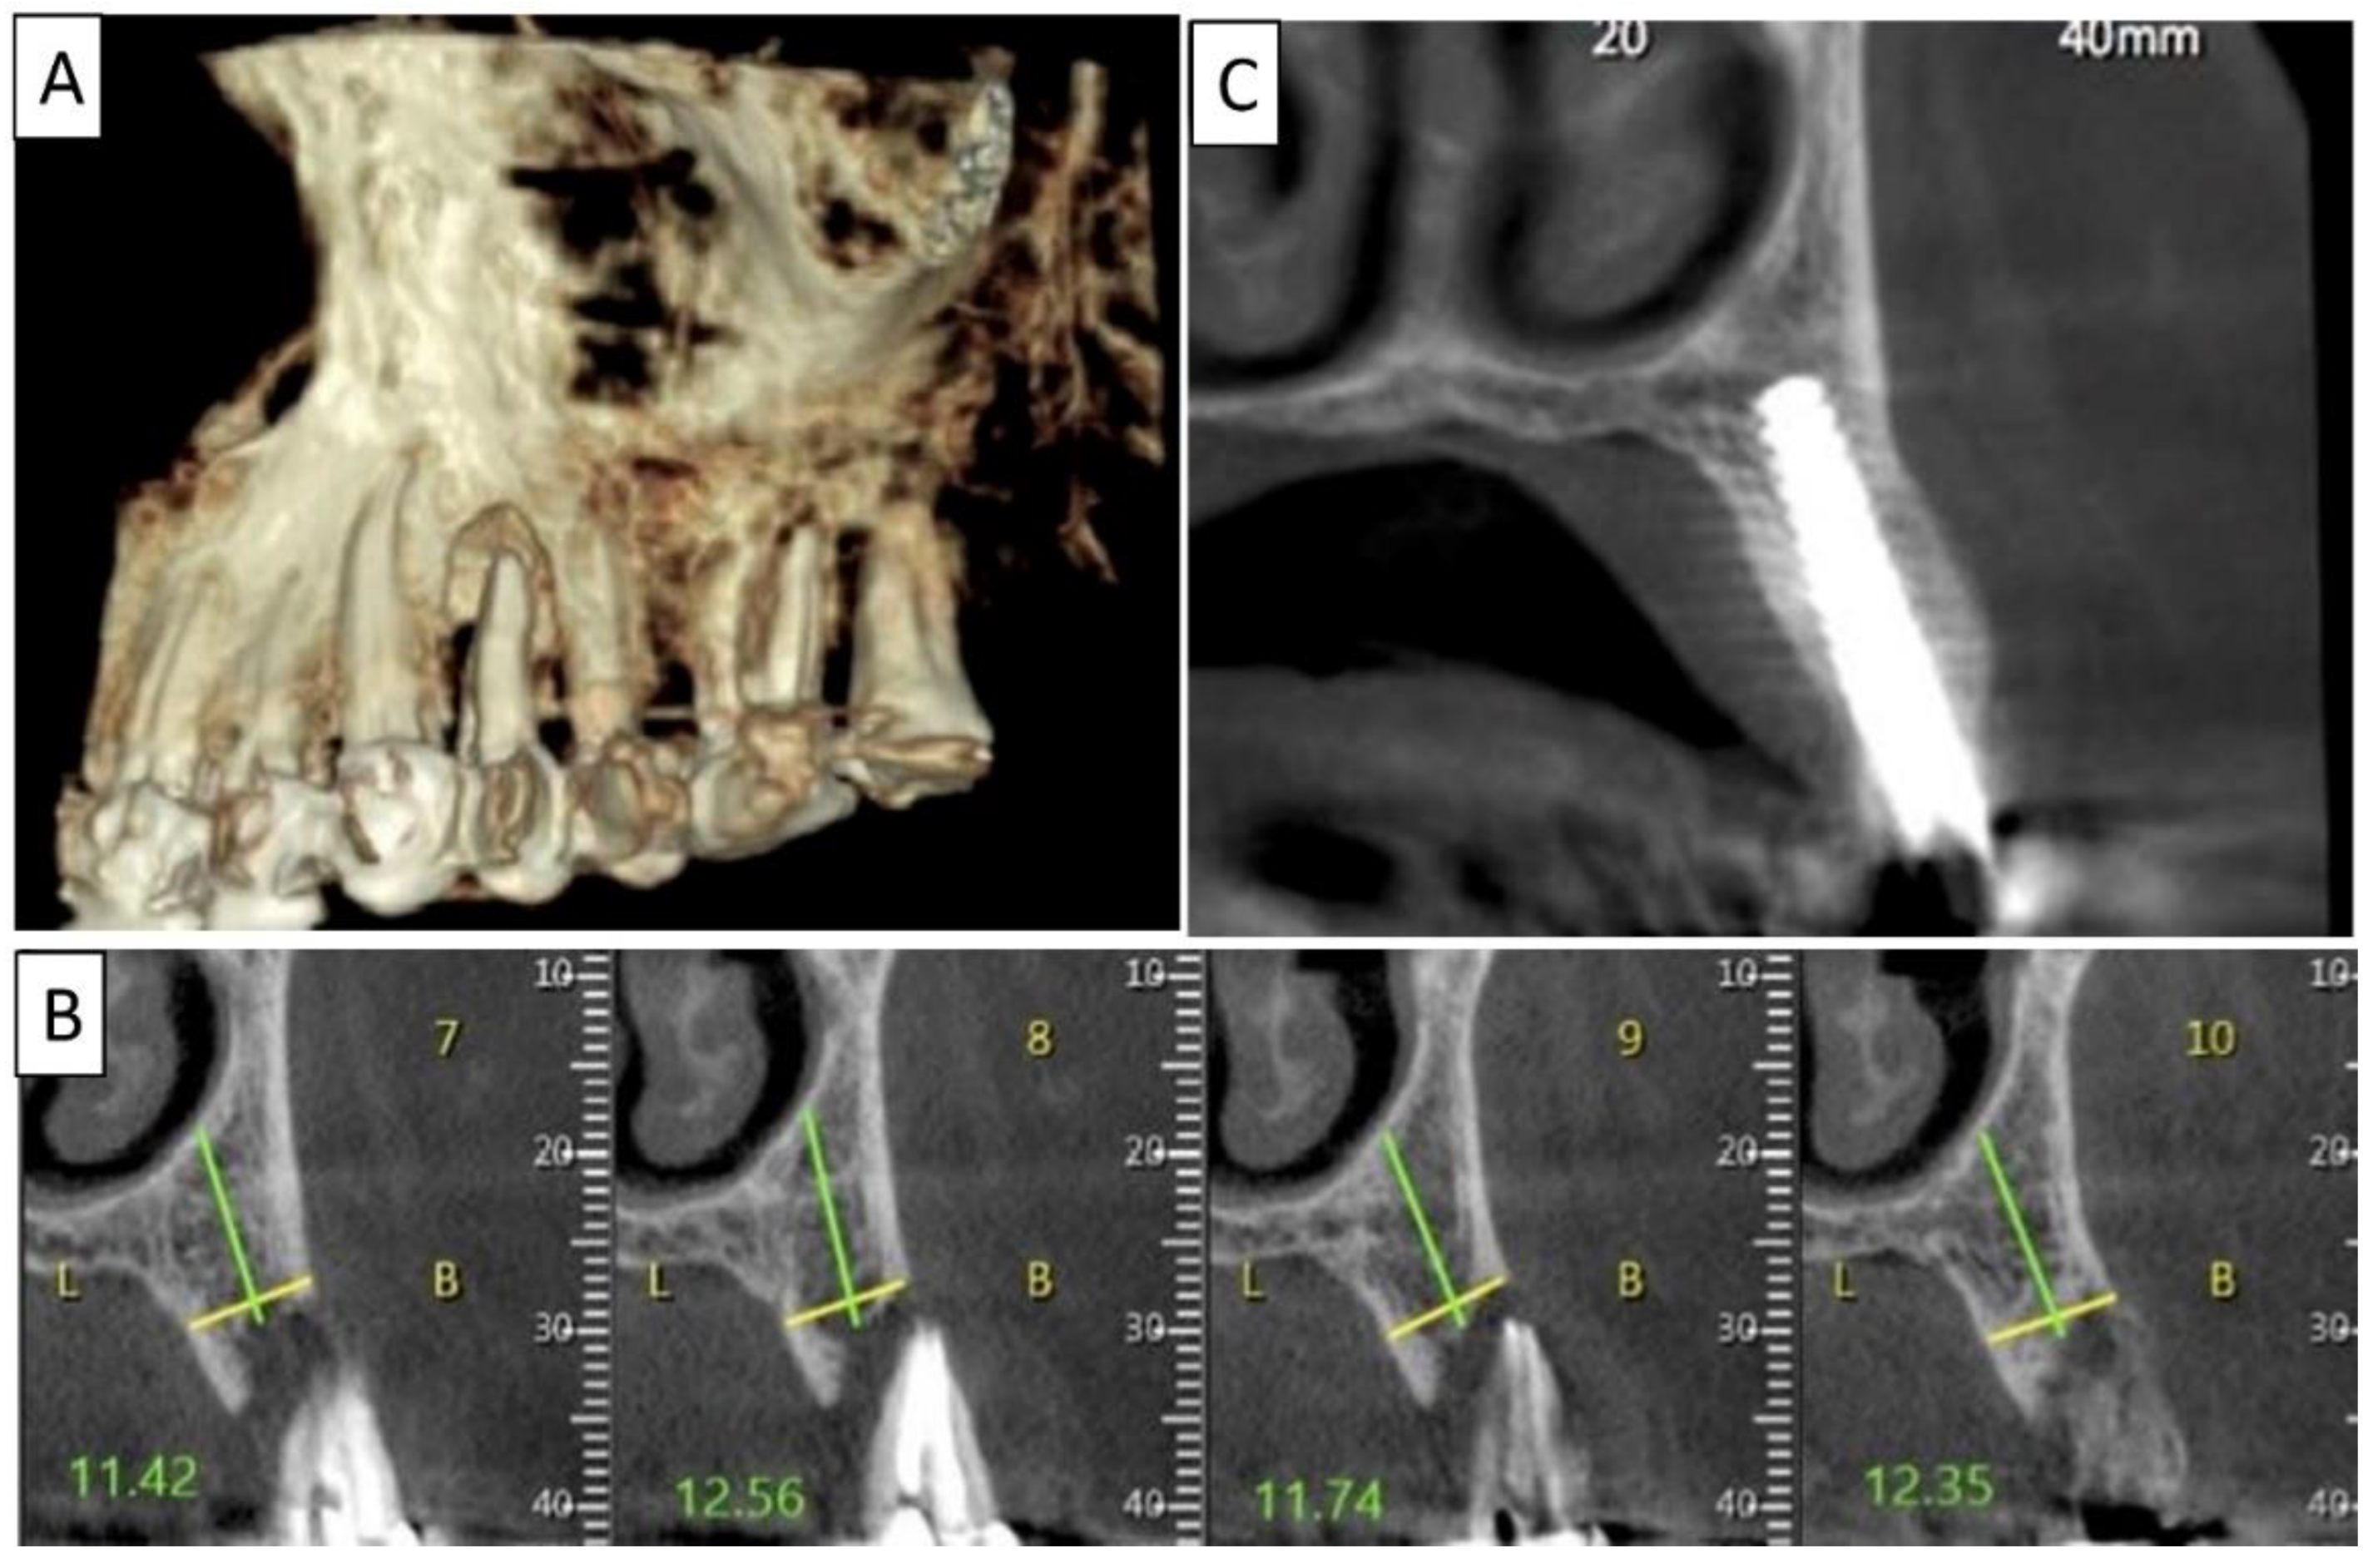

Figure 3.

(A) Lateral volumetric cone beam computed tomography (CBCT) shows significant loss of buccal and palatal bone mass around tooth 24. (B) Coronal CBCT slice of the same area of tooth 24 revealing missed buccal and palatal bone and associated apical radiolucency. (C) The coronal CBCT section shows the implant in the area of tooth 24 and the obtained completely regenerated cortical and palatal plates.